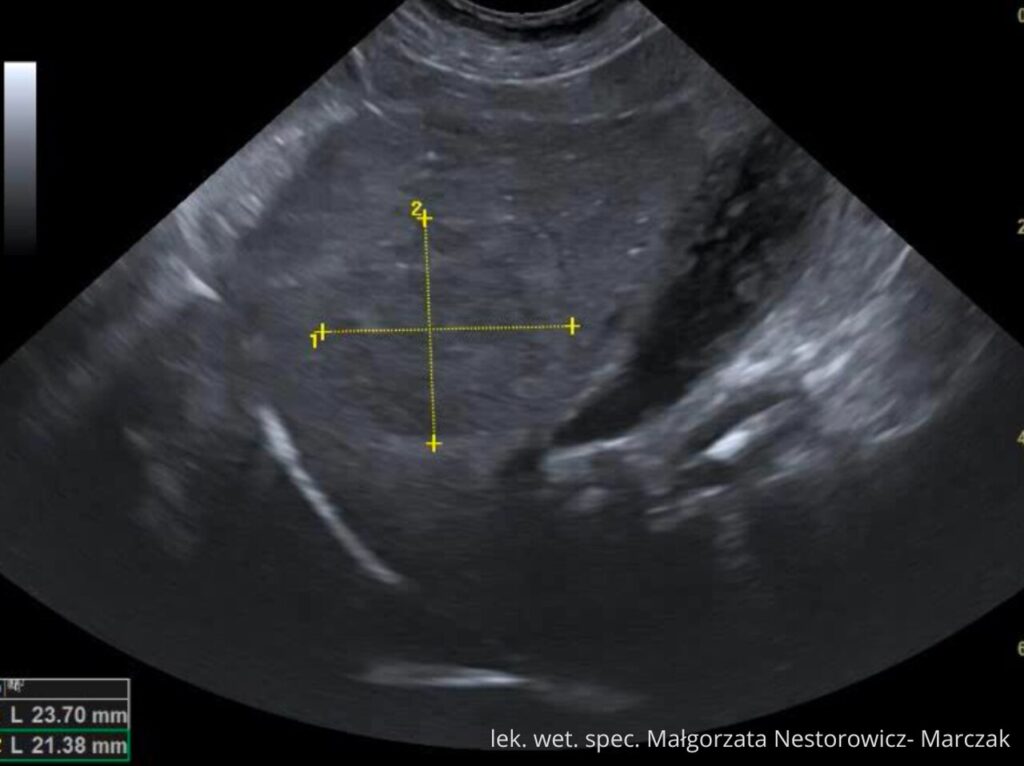

Udostępniamy cały moduł „Wątroba i drogi żółciowe” jako próbkę kursu.

To pełnowartościowy moduł szkoleniowy (niemal 2 godziny materiału), który pozwoli Ci zobaczyć, jak w praktyce wygląda nauka w kursie. Dzięki niemu sprawdzisz:

lek. wet. spec. Małgorzata Nestorowicz- Marczak

Na co dzień pracuje z małymi zwierzętami (psy, koty) w Warszawie wykonując badania USG tkanek miękkich m.in. jamy brzusznej, szyi, klatki piersiowej. Uczestniczy jako prelegent oraz trener części praktycznej w kursach USG organizowanych dla lekarzy weterynarii.